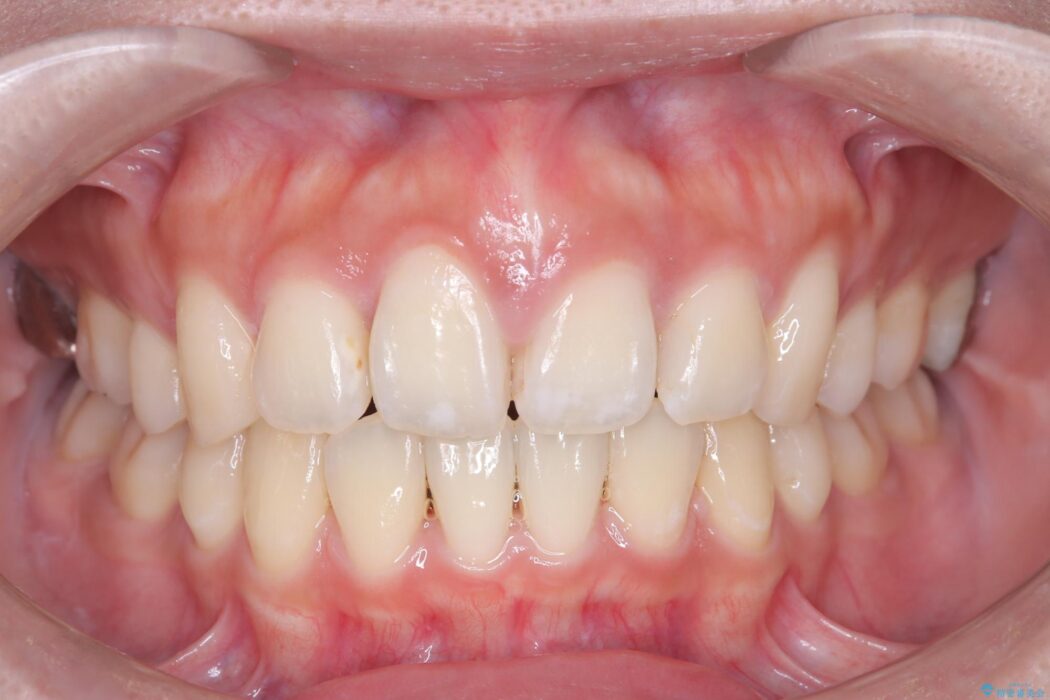

口元の突出感が解消し、Eラインが劇的に改善しました。機能的な噛み合わせと美しい審美性を両立し、理想の口元を獲得していただけました。

口元が出ていることを気にされ、ご来院された患者様です。